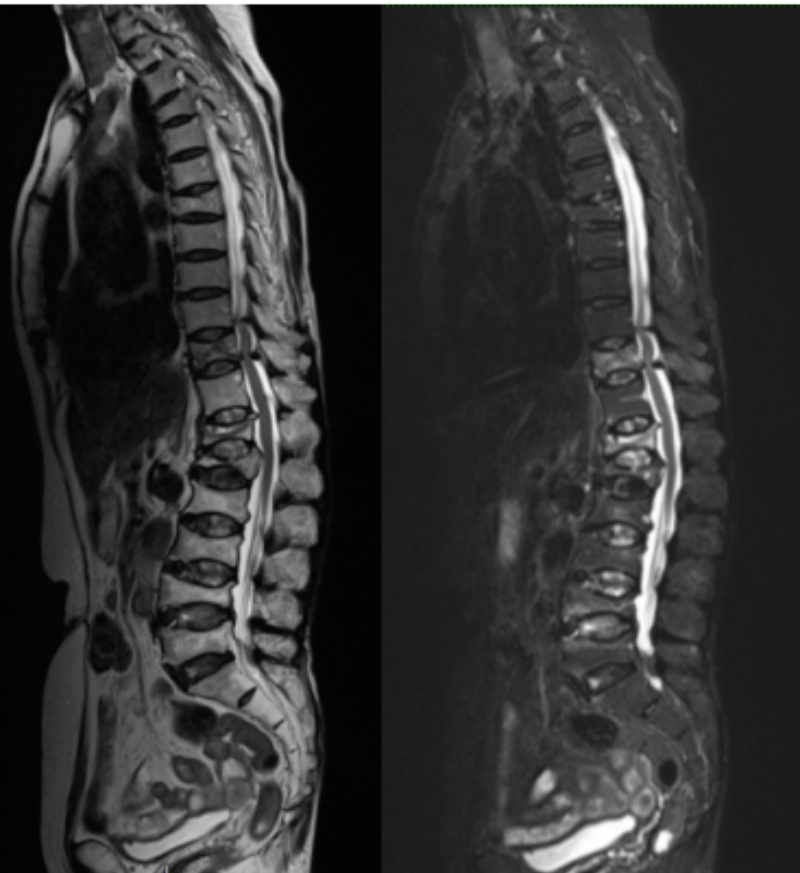

文章配圖

術前MR可見腰3/4、腰4/5椎間盤突出,伴椎管狹窄嚴重、神經根受壓、馬尾神經冗余。

最終于今年的5月份,在脊柱外科做好充分術前準備,麻醉科評估風險后,為田婆婆順利開展了手術,徹底減壓受壓的脊髓和馬尾神經,術中出血少。術后在脊柱外科醫護團隊的護理下,田婆婆恢復良好,下肢麻木感和乏力明顯好轉,術后第二天田婆婆在胸腰支具保護下下地行走。